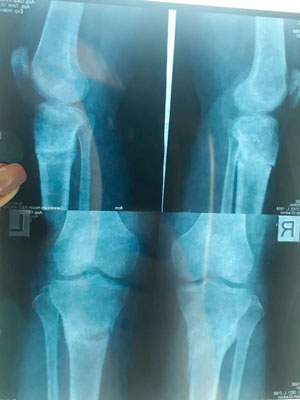

Дата операции - 04.03.2019г.

Дата снятия аппаратов - 18.06.2019г.

Срок сращения - 104 дня.